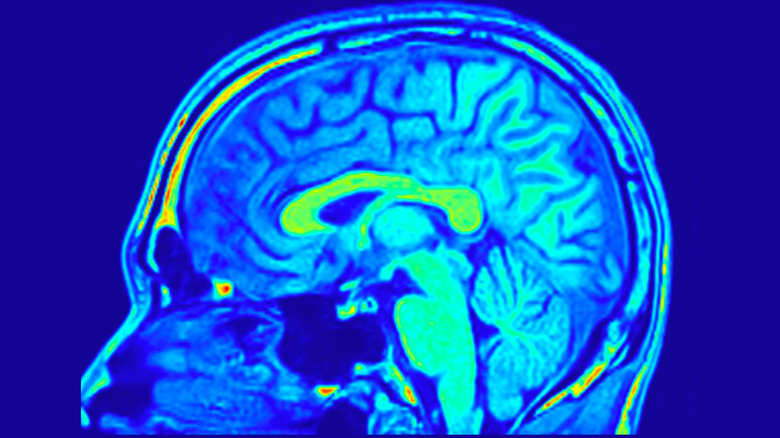

Over the last few centuries, knowledge of the anatomy of the brain has changed drastically. In the 1600s, the major sections of the brain were named by anatomists, including cerebrum, cerebellum, and medulla. In the centuries that followed, each new generation of scientists revealed something new about the brain, with technology such as the microscope and eventually modern brain scanning allowing for greater advancements to be made.

While we do use the majority of our brain throughout the day, different parts of the brain are responsible for individual tasks. The cerebral cortex at the front of the brain is responsible for movement, speech, and reasoning, and it has two sides, which each control the opposite side of the body. The brainstem in the middle is in charge of a range of functions, including hearing, breathing, and blood flow, and contains the medulla, which controls many of the vital functions that keep us alive. And the cerebellum at the back controls speech, balance, and posture. In reality, the majority of your brain is working hard for most of the day to keep you functioning, so if you had plans to uncover superhuman powers by engaging more of your brain, you may be disappointed.